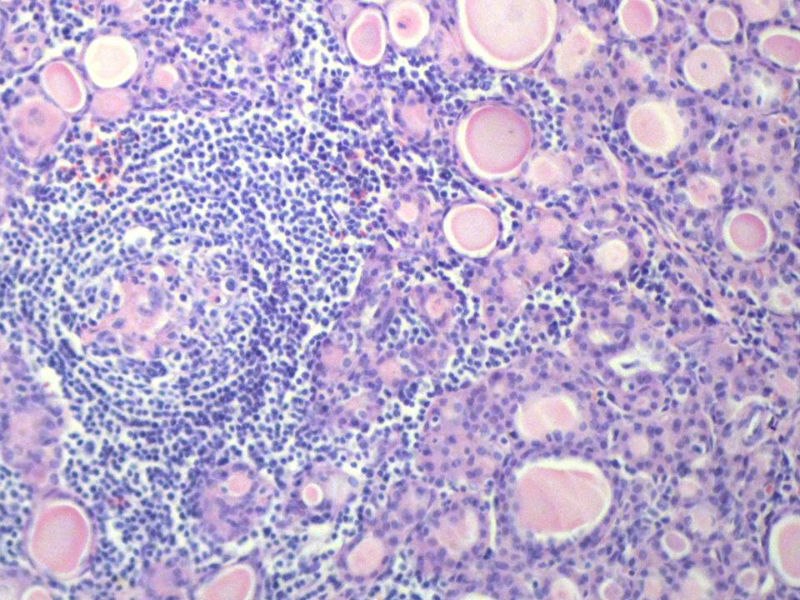

女,60岁,右侧甲状腺肿物两个月,术中见肿块与周围组织无粘连,肉眼,灰红色组织,3X2X2厘米,切面见一直径2.5厘米肿物,包膜完整,灰黄色,质软。

具有桥本氏病的大部分特征,有结节形成,此情况有称之为“结节性桥本甲状腺炎”